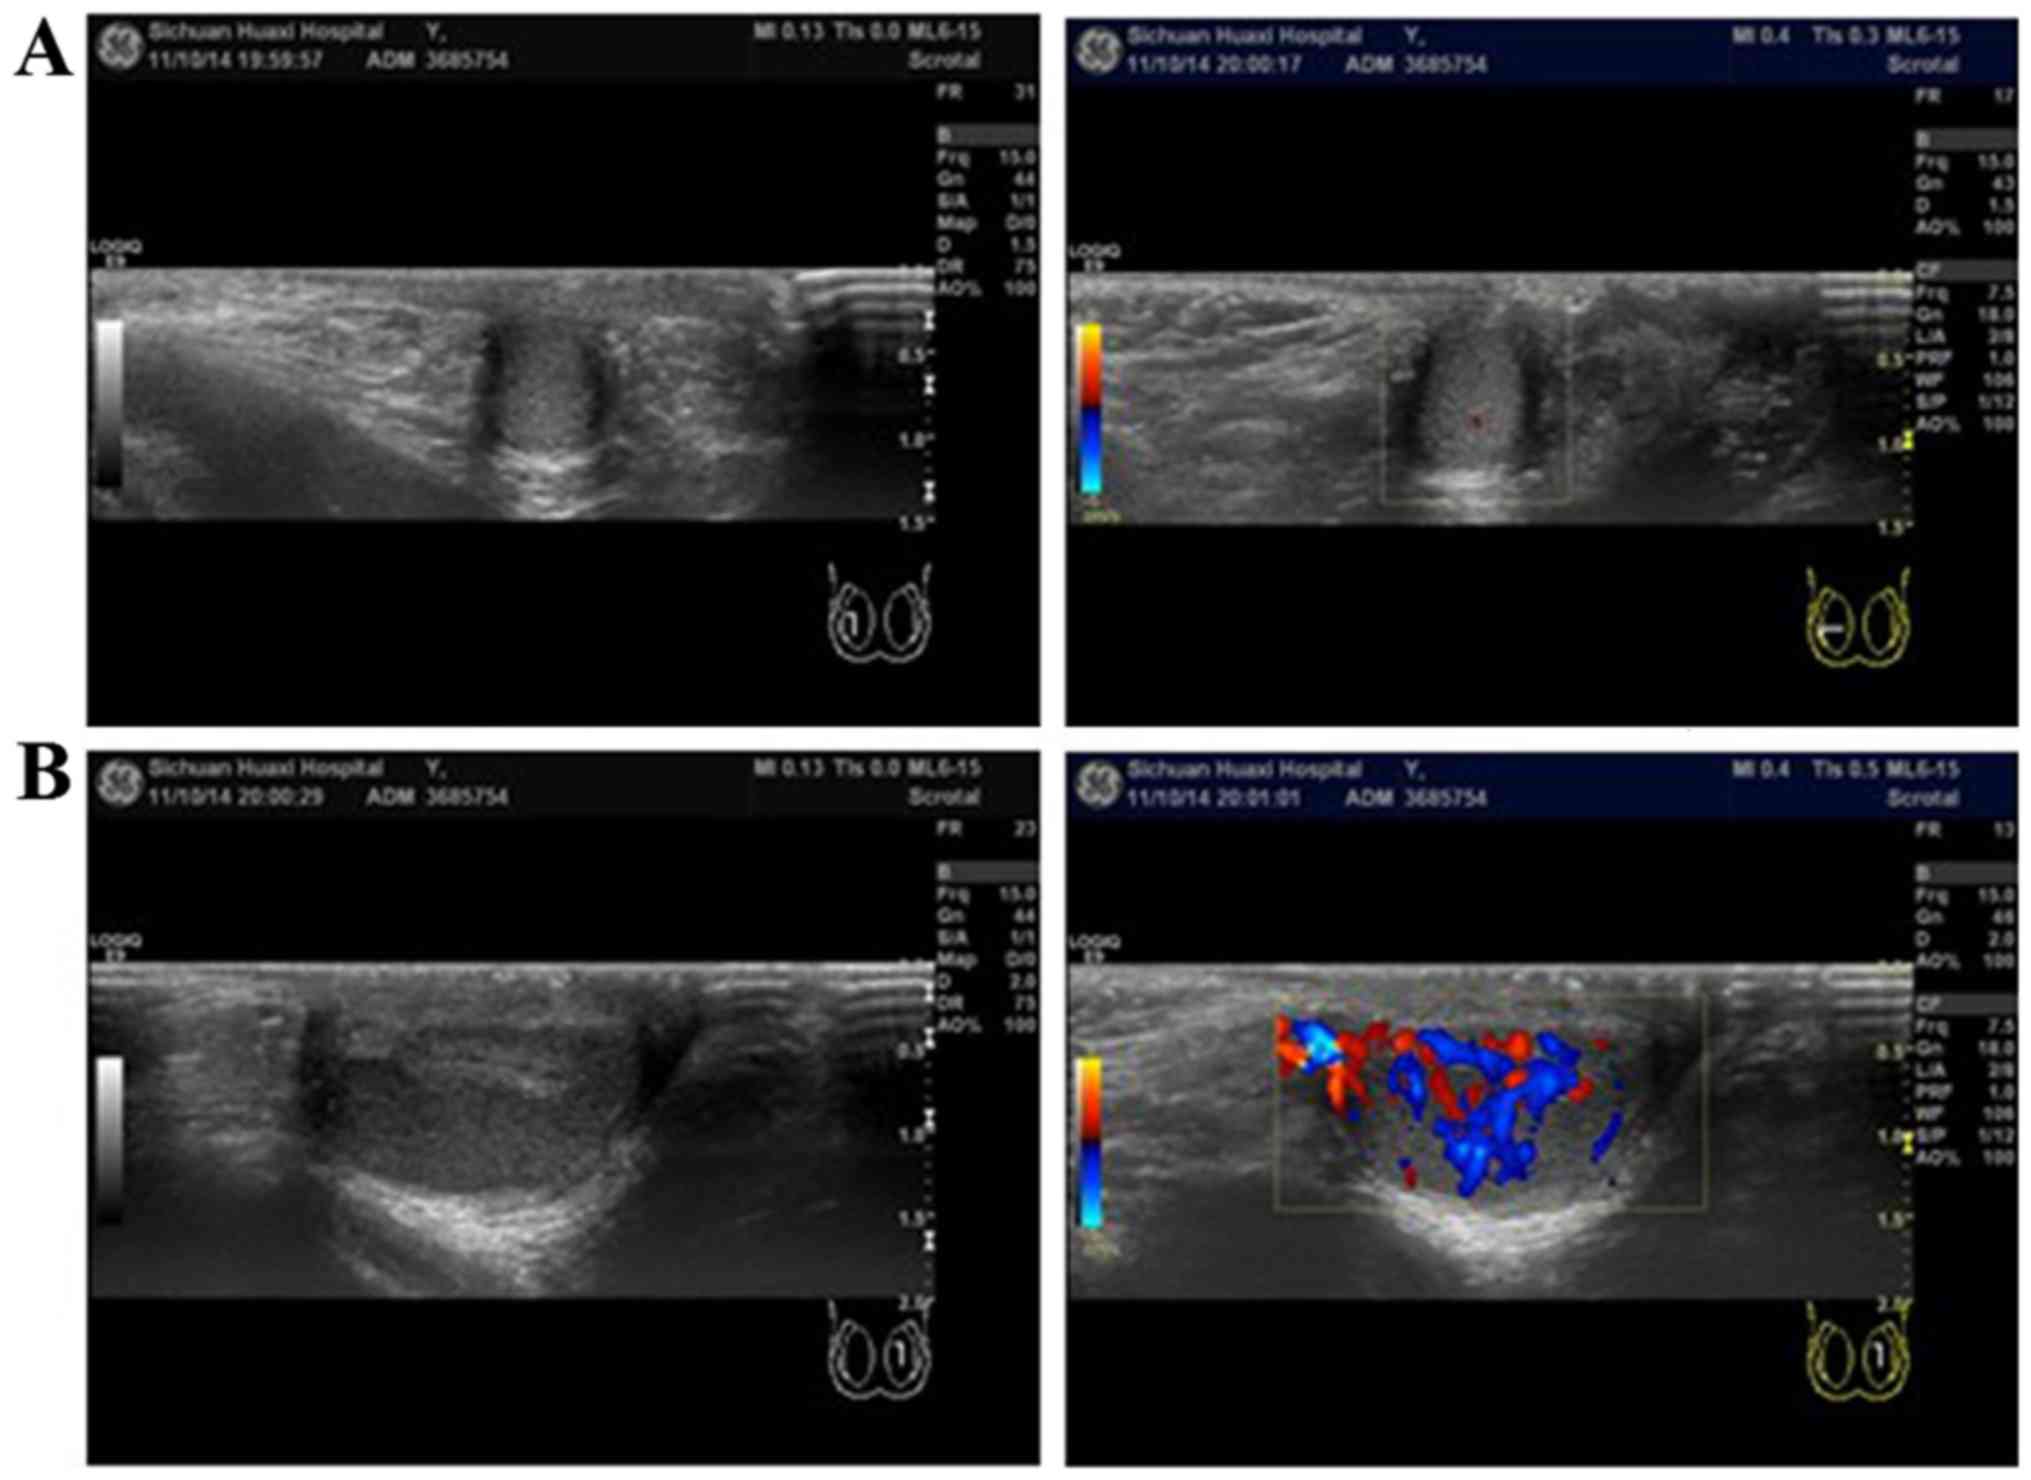

A 4-year-old boy presented to the Department of Pediatric Surgery, West China Hospital of Sichuan University (Chengdu, China) with bilateral undescended testes from birth in April 2013. Physical examination indicated that the bilateral scrota were empty, the testes were also not present in the inguinal region, and the patient's penis was normal. An ultrasound confirmed that there were no testicular masses in the bilateral scrota and inguinal regions. In accordance with the above clinical findings, the patient was diagnosed with bilateral cryptorchidism, and therefore laparoscopic gonad exploration was performed. Complete abdominal exploration revealed gonad-like tissue connected with a smooth, fleshy, brown, cord-like structure beside the left colon, but left spermatic cord blood vessels were not observed. The cord-like structure was connected to the spleen (which was normal), and was approximately 5–6 cm long and 1.5 cm in diameter (Fig. 1A and B). The spleen cord was cut off and the gonad-like tissues were pulled down into the scrotum through the inguinal canal (Fig. 1C-E). A small incision was made in the scrotum skin to expose the gonad-like tissue. A small piece of gonad-like tissue was harvested for pathological examination. The result of pathological examination demonstrated that the gonad-like tissue was a normal testis. As a result, the spleen cord was resected and Fowler-Stephens orchidopexy was implemented. The right testicle was located in the right iliac fossa, 2 cm from the right deep inguinal ring. The right spermatic cord was short and the testis exhibited dysplasia. The right testicle was moved posteriorly and fixed by single-stage laparoscopic Fowler-Stephens orchidopexy (Fig. 1F). Postoperatively, the patient recovered well. At a 6-month follow-up in the Outpatient Department of Pediatric Surgery, West China Hospital of Sichuan University physical examination revealed that the right testis was normal; however, the left scrotum demonstrated swelling and the internal contents were hard. An ultrasound of this testicle indicated non-uniform, splenic-like organization, with abundant blood flow and a reduction in the testicular size (Fig. 2). We will continue to follow-up this patient; if hyperplasia of the splenic tissue in the scrotum is detected during a subsequent follow-up, a reoperation will be performed. At one-year follow-up, the volume of splenic-like organization was reduced but the testicular size did not exhibit further atrophy, thus reoperation has not been performed. We will continue to follow-up this patient.